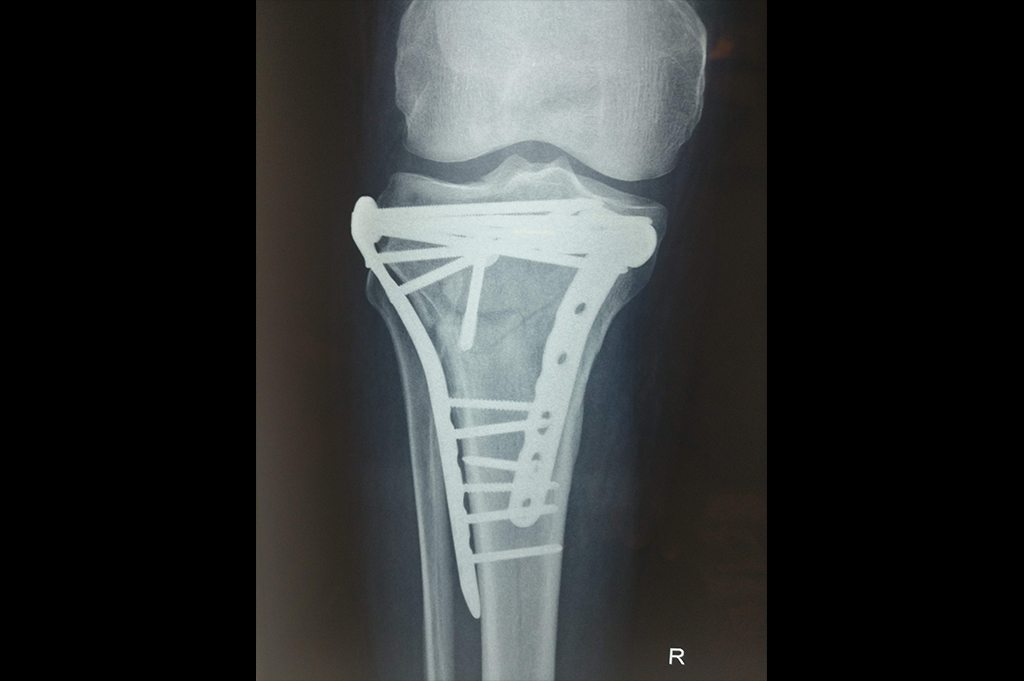

Proximal Tibia